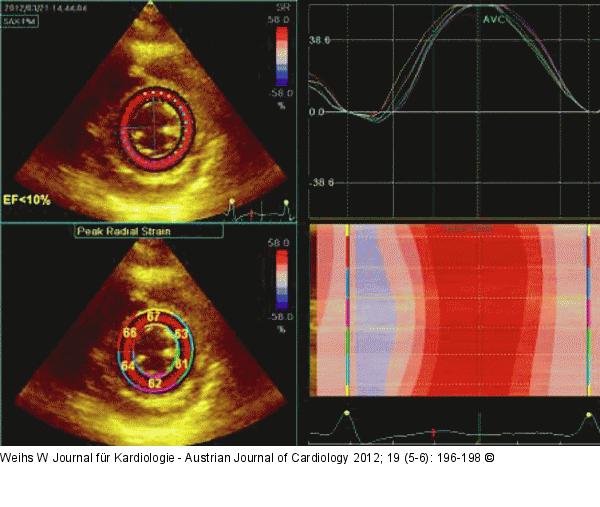

Abbildung 10: Speckletracking Speckletracking des linken Ventrikels: Gesteigerte radialer Strain im Querschnitt (Hyperkontraktilität). |

Speckletracking des linken Ventrikels: Gesteigerte radialer Strain im Querschnitt (Hyperkontraktilität). |